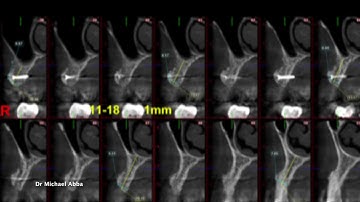

Horizontal GBR with Titanium Mesh and Tenting Screws